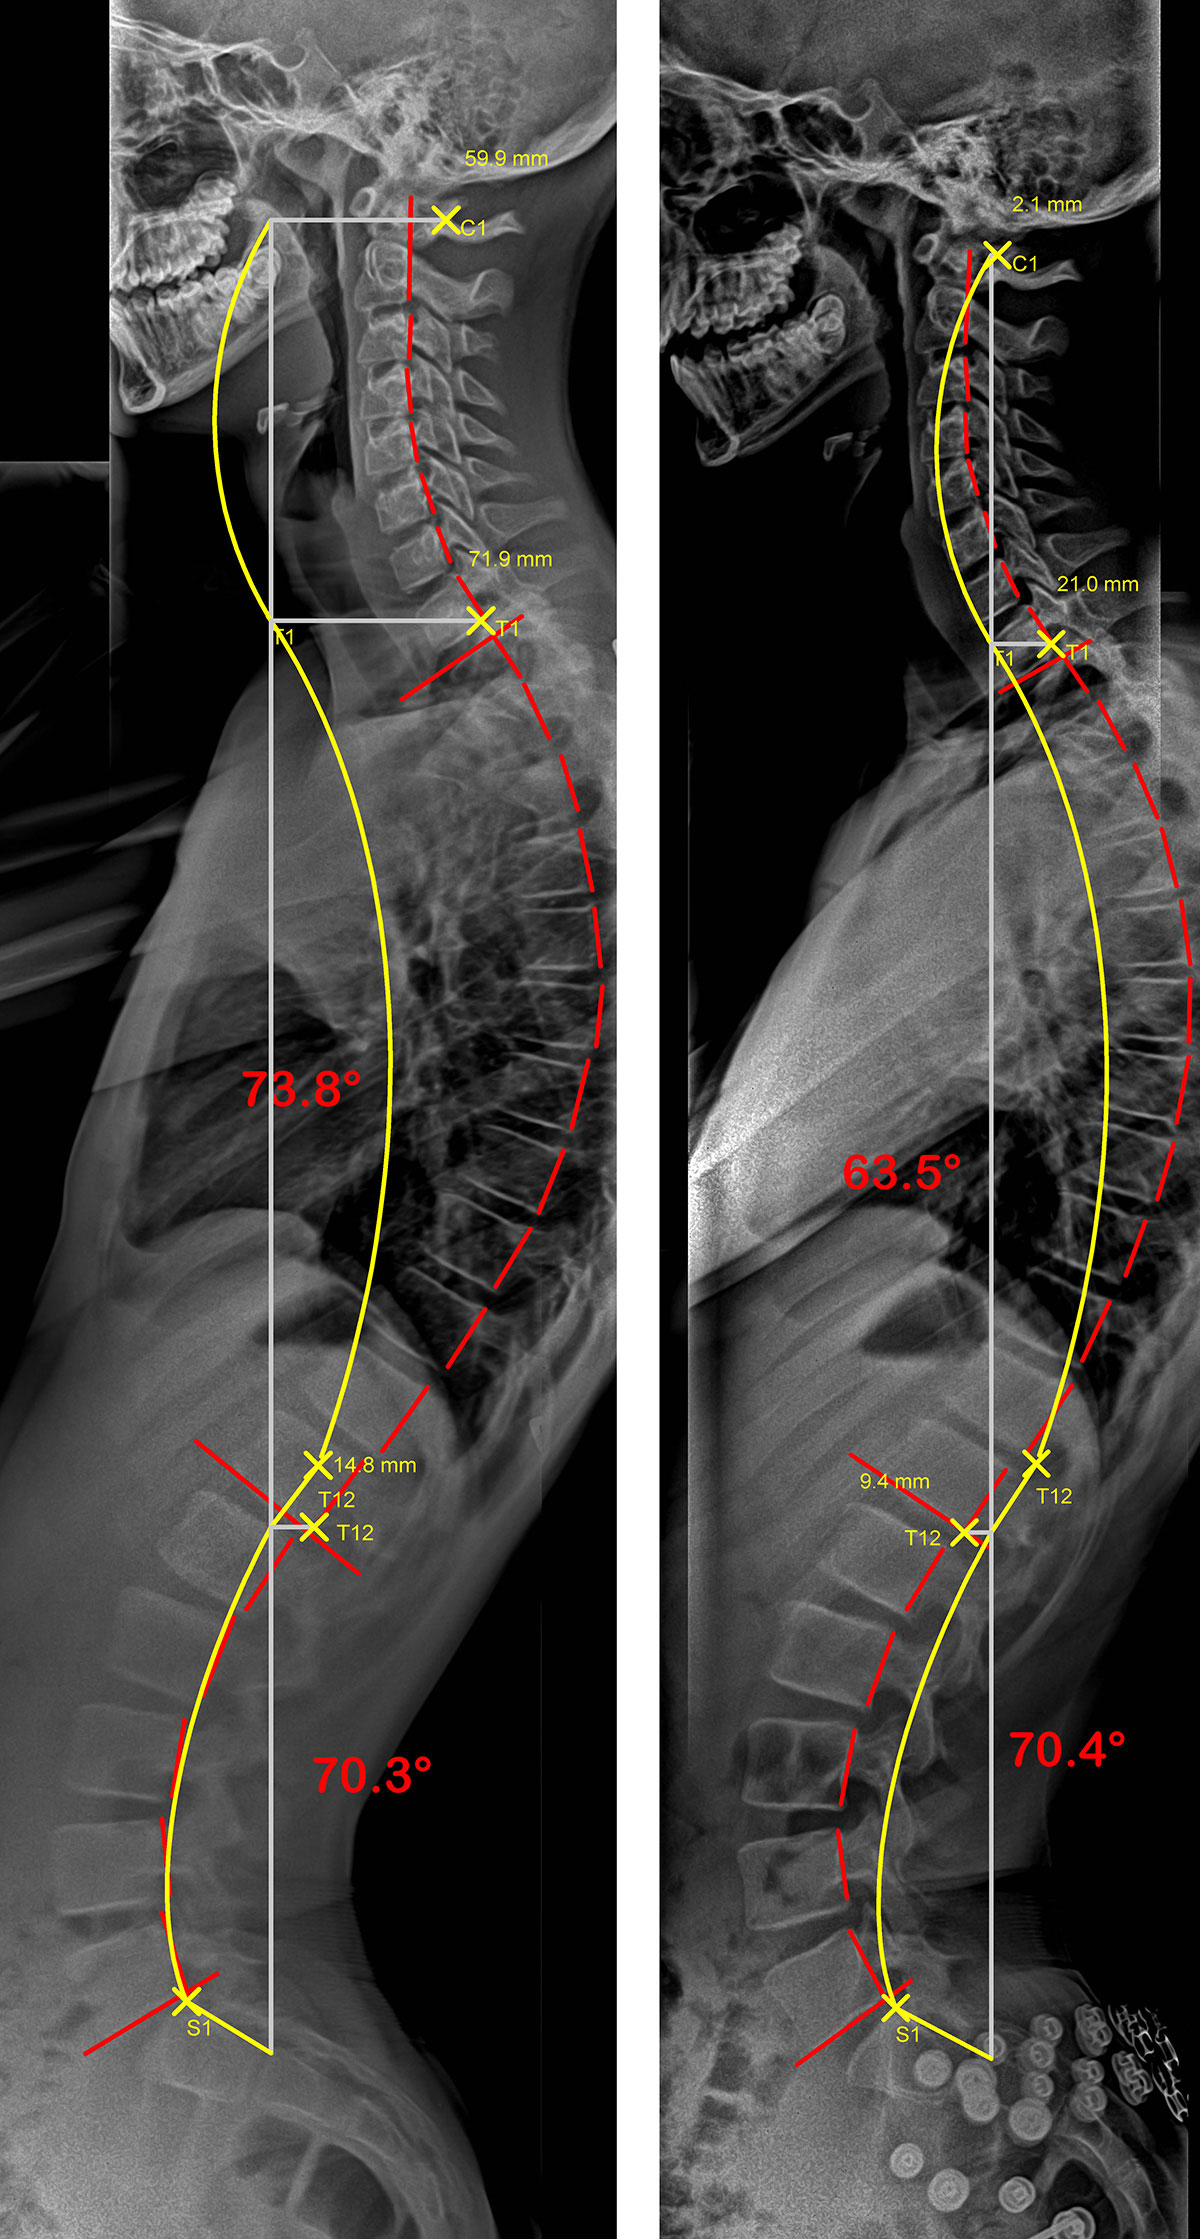

Colonne vertébrale d’un adulte souffrant d’hypercyphose, sans et avec SpineCor®

Radiographies de profil d’un patient présentant une hypercyphose. La ligne jaune représente la courbure idéale et la rouge, celle formée par la colonne vertébrale du patient. Dans la seconde radiographie où le patient porte son SpineCor®, on remarque une amélioration significative de la courbe anormale.